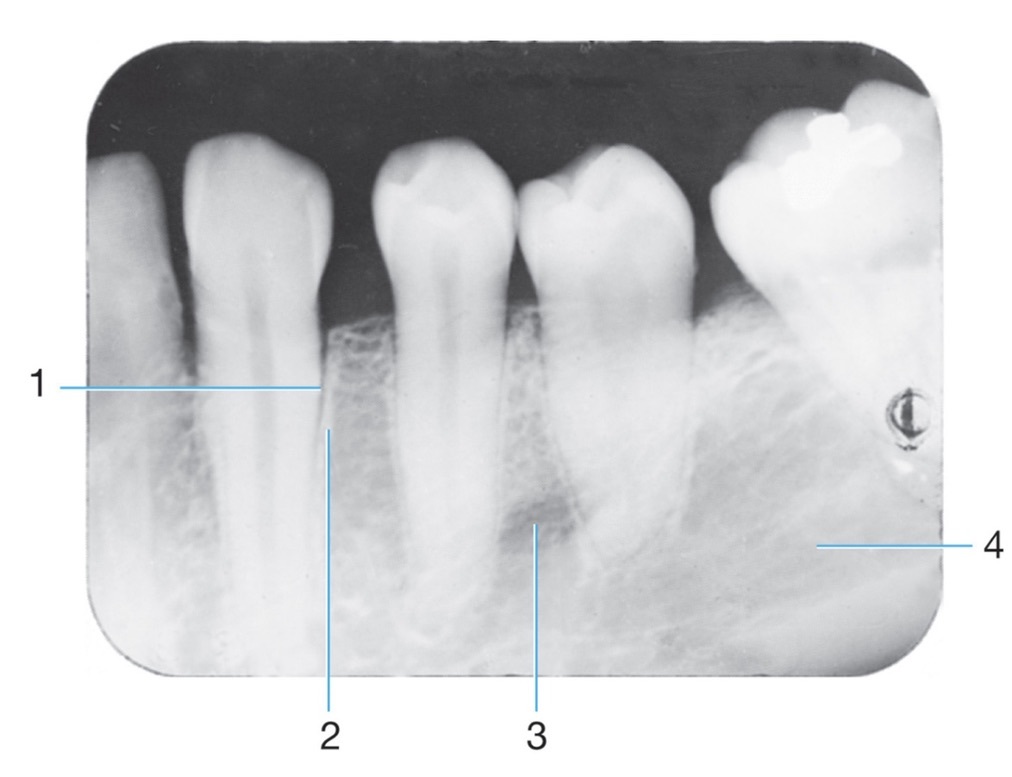

1.

Amalgam

Identify #1.

Border of maxillary sinus

Linear prominence of bone located on the internal surface of the mandible that extends downward & forward from the ramus?

Radiolucent/Radiopaque?

Internal oblique ridge

Radiopaque

PDL space

2.

Mylohyoid ridge

4

Identify the following: